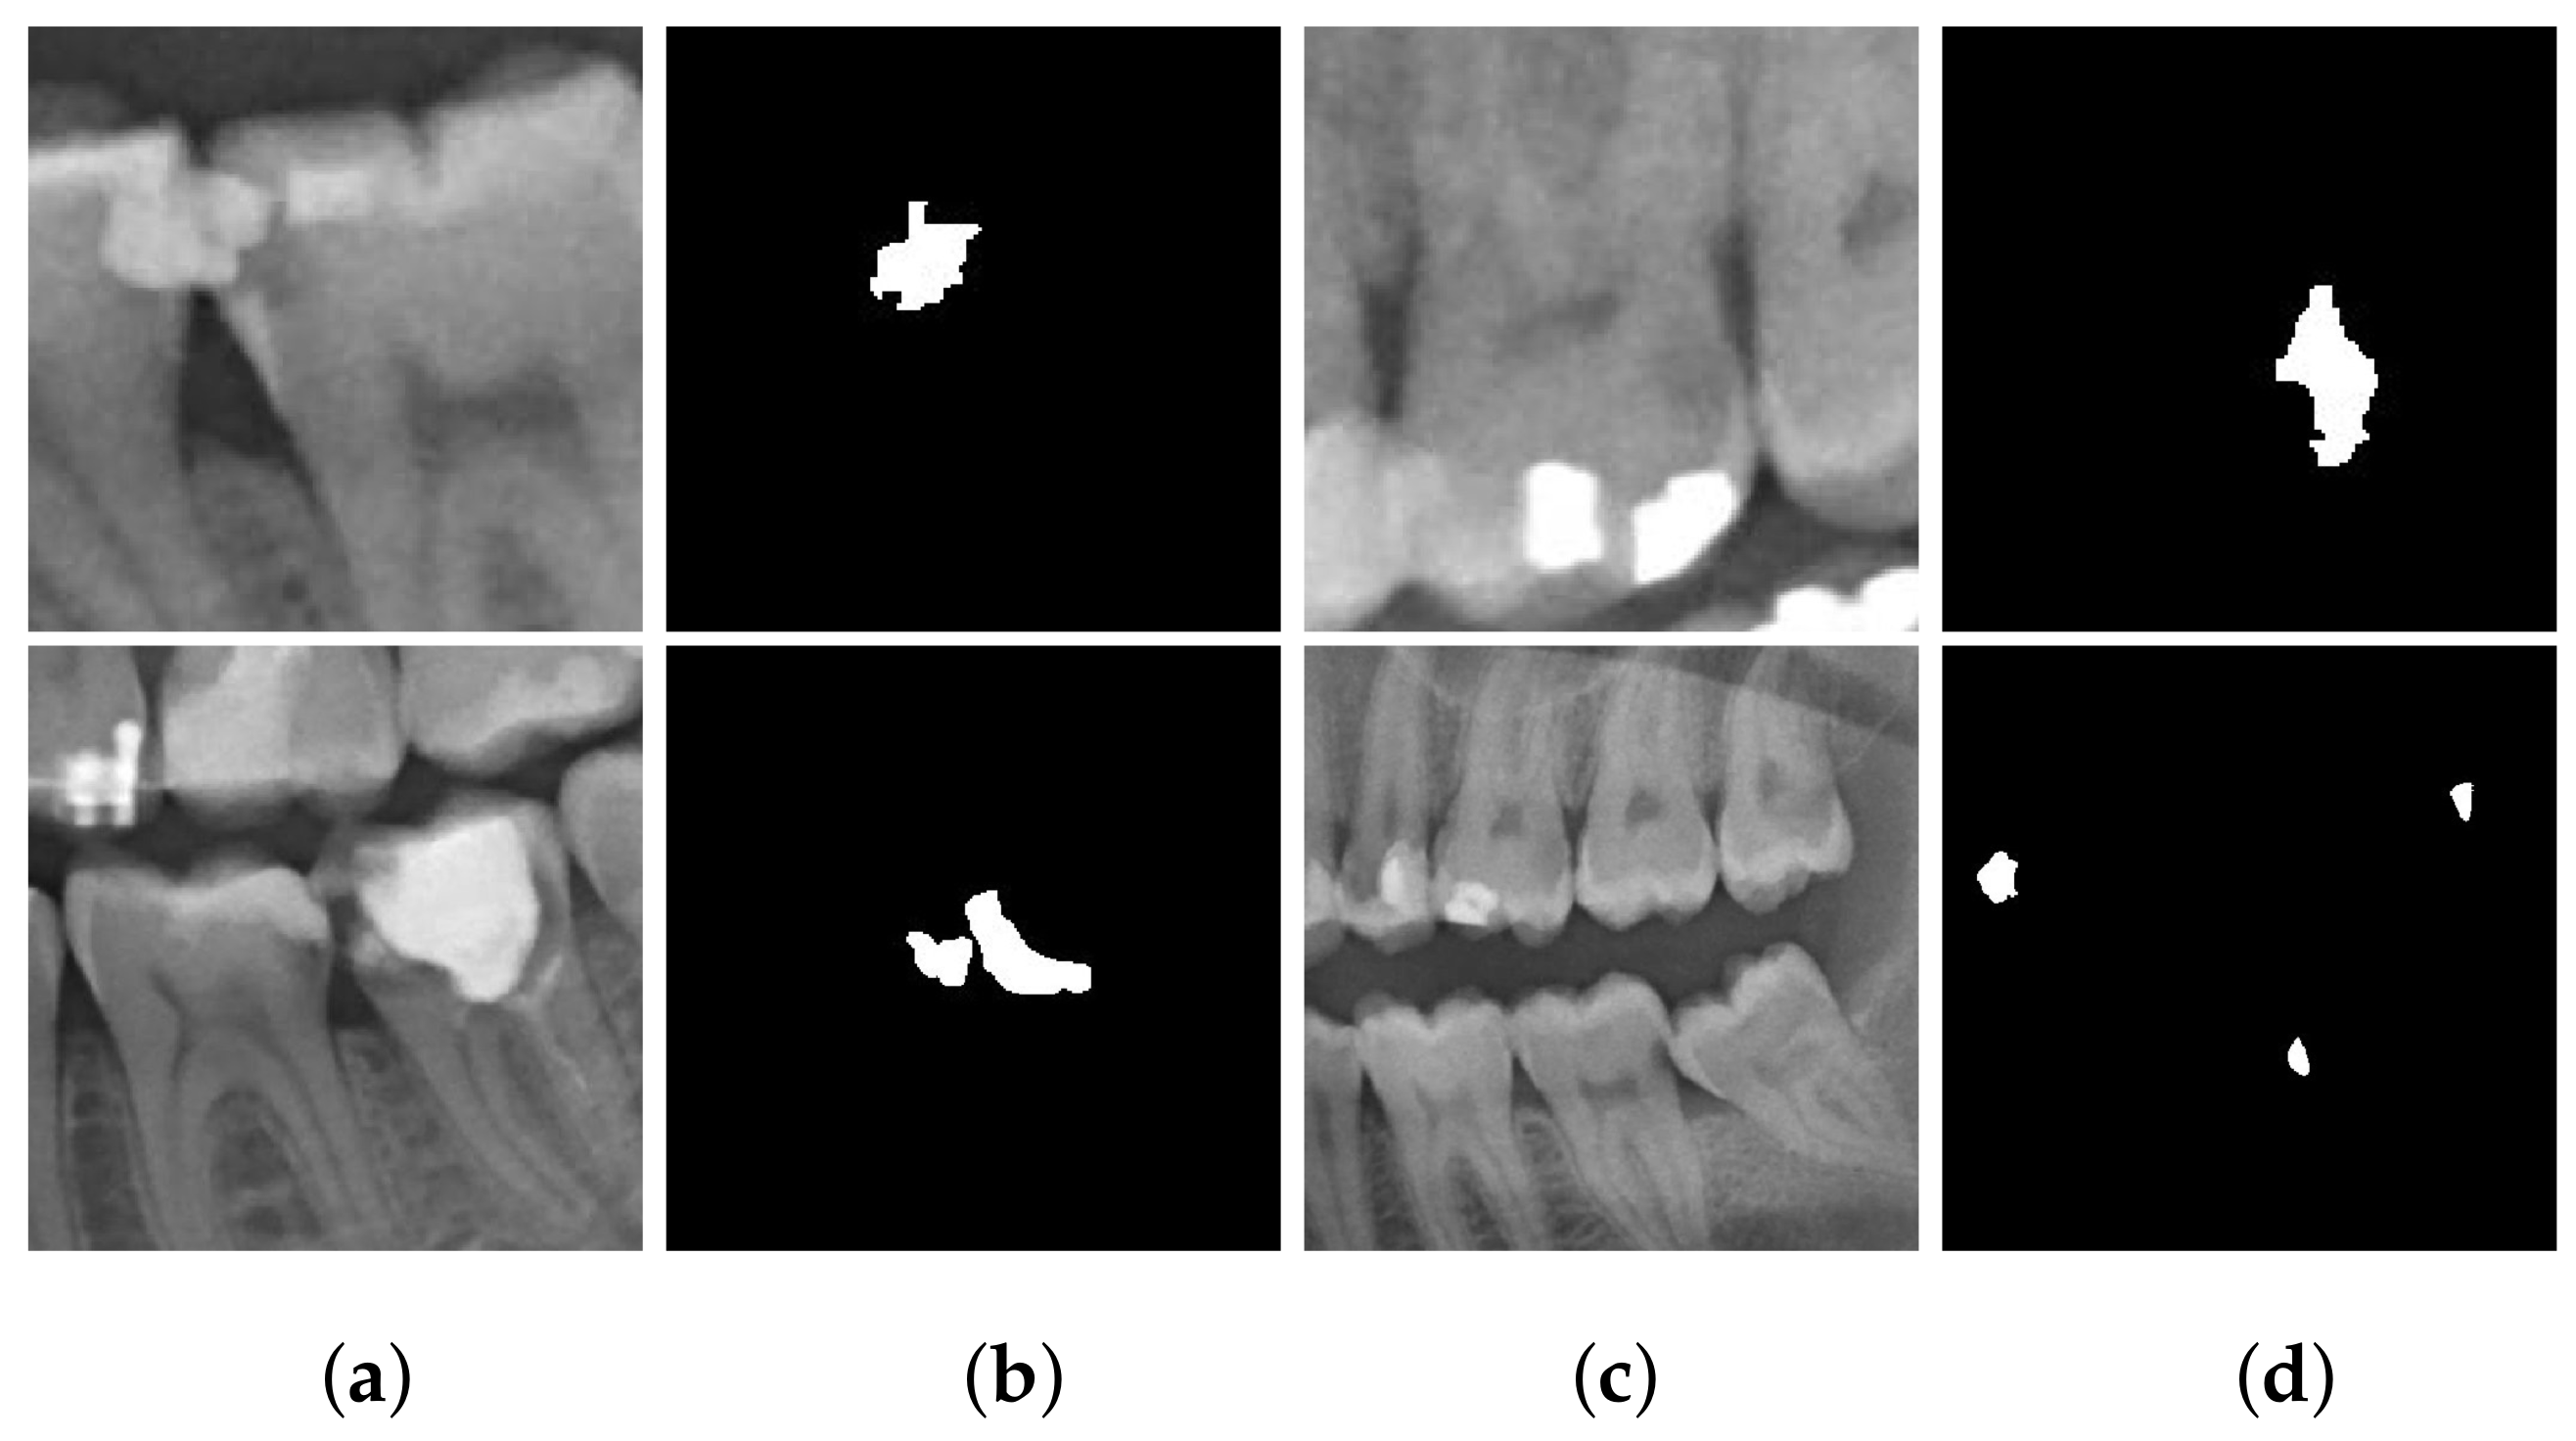

From www.mdpi.com

Applied Sciences Free FullText Detection of Cavities from Dental Dental Panoramic X Ray Cpt Code  This guide is published to educate dentists and others in the dental community on selection and reporting of diagnostic imaging procedures. Code on dental procedures and nomenclature effective january 1, 2022 d0367 cone beam ct capture and interpretation with field of view of. The d0220 dental code, officially recognized by the american dental association (ada), refers to the procedure for.. Dental Panoramic X Ray Cpt Code.

Applied Sciences Free FullText Detection of Cavities from Dental Dental Panoramic X Ray Cpt Code  This guide is published to educate dentists and others in the dental community on selection and reporting of diagnostic imaging procedures. Code on dental procedures and nomenclature effective january 1, 2022 d0367 cone beam ct capture and interpretation with field of view of. The picture shows all the. D0210 is typically paid once every three to five years. A radiographic. Dental Panoramic X Ray Cpt Code.

Applied Sciences Free FullText Detection of Cavities from Dental Dental Panoramic X Ray Cpt Code  The picture shows all the. The d0220 dental code, officially recognized by the american dental association (ada), refers to the procedure for. Code on dental procedures and nomenclature effective january 1, 2022 d0367 cone beam ct capture and interpretation with field of view of. This guide is published to educate dentists and others in the dental community on selection and. Dental Panoramic X Ray Cpt Code.